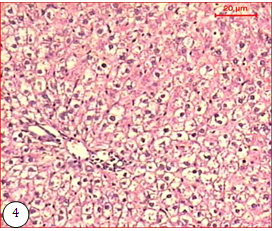

Healthy rats treated with both cold and hot algal extracts showed normal hepatic lobular architecture with normal hepatocytes. No hydropic or steatosis changes were seen, and portal tracts were within normal limits, and no sign of fibrosis was detected (Figs. 2, 3). In HC-rats, the hepatic cords of rats were disorganized, and large numbers of liver cells were swollen and had undergone hydropic degeneration. Different sizes of fat droplets and fatty degeneration of the liver were observed in the cytoplasm of hepatocytes from hyperlipidemic rats. Inflammatory cell infiltrations along with spotty and patchy necrosis of hepatocytes were also observed in the lobule and portal areas (fig. 4). Hepatocytes of HC rats showed severe degeneration with diffuse vacuolar degeneration and necrosis.

Fig. 4: Micrograph of liver of HC shows fatty change of the hepatic lobule and hydropic degeneration (H & E X 150) |

The effect of U. fasciata on hepatocyte cells of HC rats is presented in (fig. s: 5, 6). The hepatic cords were typically arranged and located in liver tissue near the central vein in the normal control (NC), HC, and HC+SP groups. Hepatic cells of HC rats treated with both cold and hot SP extracts were improved with fewer endothelium injuries and less fat vacuoles, showed a considerable reduction in the pathological changes and exhibited an almost normal fig. as the control and the hydropic degeneration of the hepatocyte disappeared. The circular fat droplets in the cytoplasm decreased significantly, and only minor inflammatory cell infiltration was observed in portal areas.

These biochemical findings were associated with significant improvement in the cellular architecture of both liver and kidney. Histological investigations showed that the HC-rats displayed an important lipid droplet accumulation and both UFPs dramatically reduced in a dose-dependent manner the number of hepatocytes that contain lipid droplets. It was found that lipid droplets were observed only in the liver tissue of HC rats [79]. This could be attributed to lipid accumulation in the hepatocyte cell cytoplasm. Oxidized LDL induces the expression of scavenger receptors on the macrophage surface. These scavenger receptors promote the accumulation of modified lipoproteins, forming an early atheroma [80]. Ballooning of hepatocytes deformed cord arrangement, and disturbed sinusoids were seen Hepatocytes of HC rats showed severe degeneration with diffuse vacuolar degeneration and necrosis. Lipid droplets were observed only in the liver tissue of HC-rats. This could be attributed to lipid accumulation in the hepatocyte cell cytoplasm.